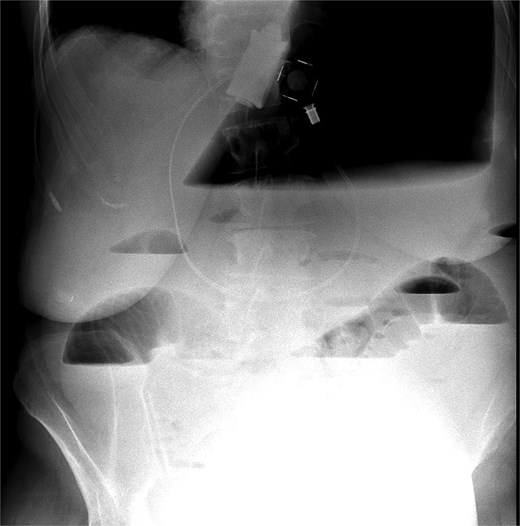

The CT also showed a large ventral hernia in the anterior abdominal wall on the left side, with several entrances and exits for intestinal loops within the hernia. The proximal loops appeared dilated up to 5 cm, with fat stranding and slight fluid between the loops, as well as mild prominence of the mesenteric blood vessels. Distal loops were collapsed, raising suspicion of high-grade obstruction with ischemic bowel involvement (Fig. 5).

CT axial view—obstructed ventral hernia with proximal small bowel loop dilatation.